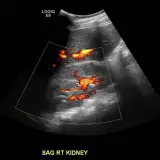

Over 2,100 interactive radiology cases, curated by radiologists for your level of training. Scroll, window, and view cases full screen — just like on PACS. Click linked findings in each writeup to jump straight to them on the image. Cases include sample reports, a focused discussion section, original illustrations, and videos.

完全交互式病例,配备您在 PACS 上期待的各项工具——滚动、调窗、缩放、平移、测量、ROI 和全屏模式。

丰富的标注直接在病例图像上突出关键发现。点击病例讲解中的关联发现,即可跳转至其在扫描上的精确位置。